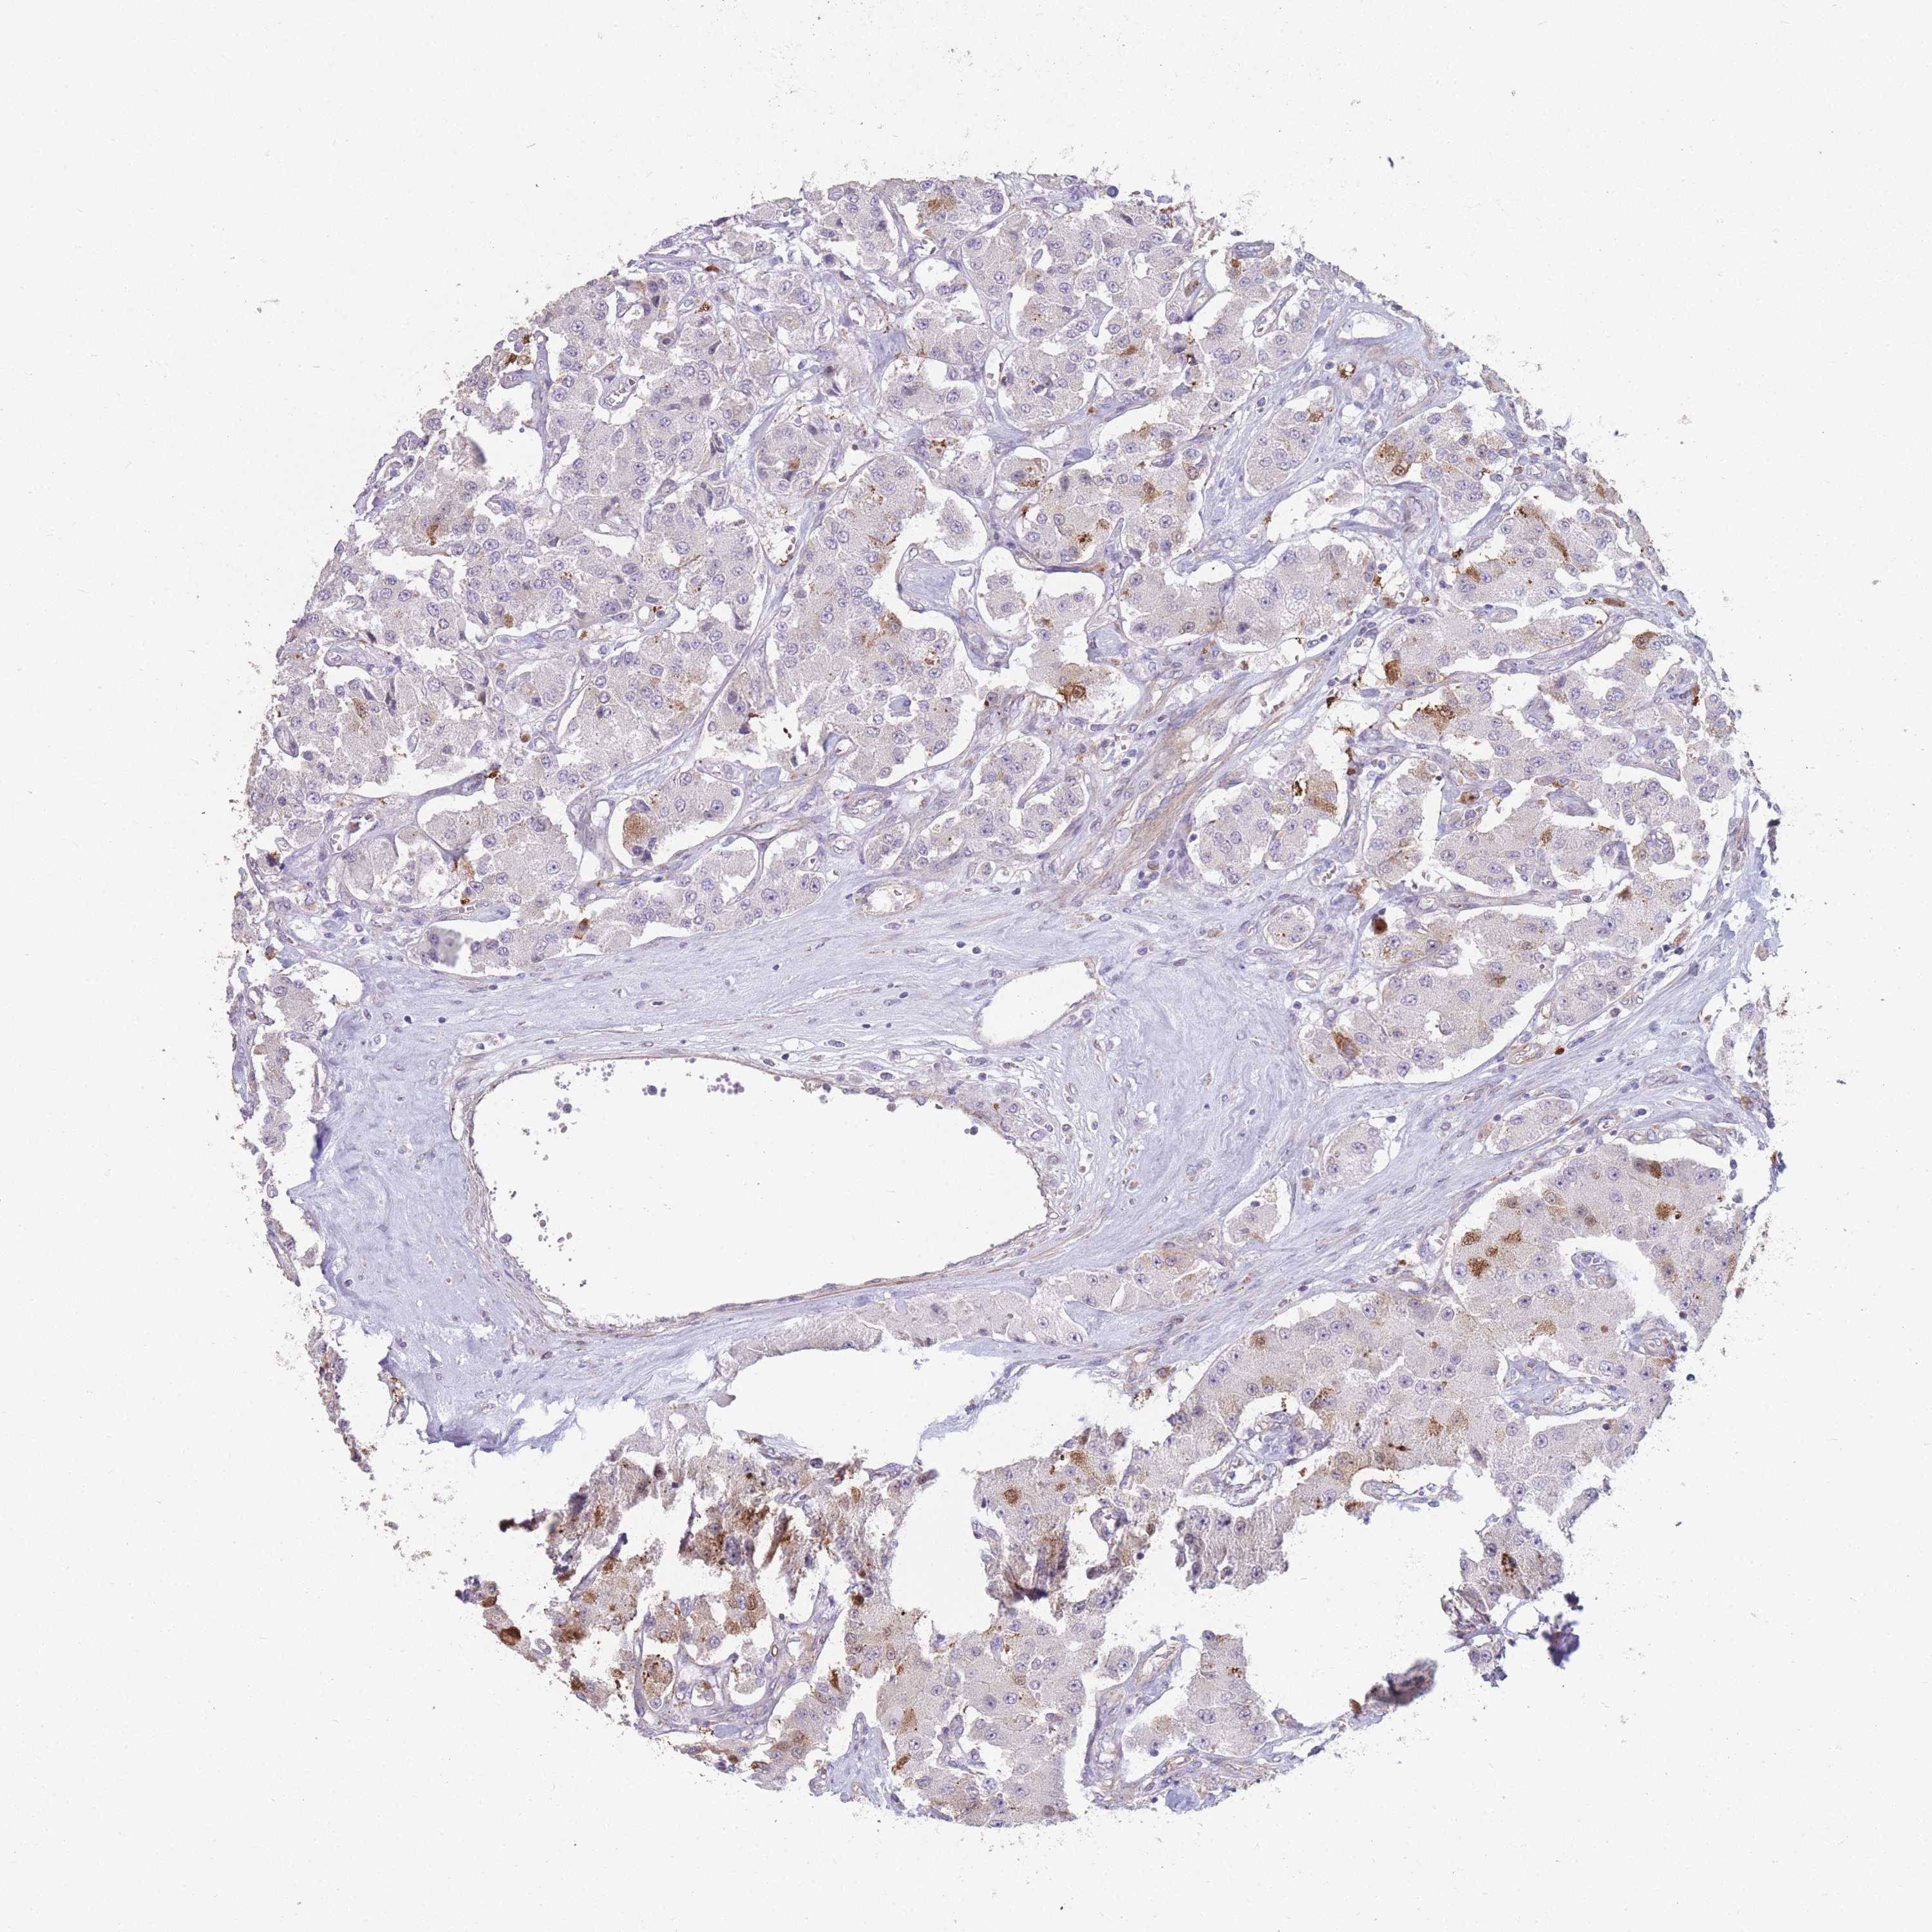

Neuroendocrine tumors

Human pathology

Carcinoid